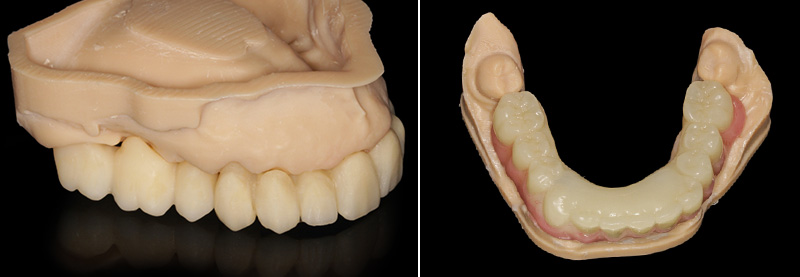

L’infrastructure maxillaire en zircone a été stratifiée manuellement à l’aide d’une vitrocéramique composée de disilicate de lithium. Le montage des dents en résine et la réalisation de la fausse-gencive rose à la mandibule ont été réalisés manuellement avant polymérisation selon une technique conventionnelle.

Fig. 11 : confection des prothèses d’usage.